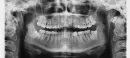

Мой ортодонт посоветовала удалить все 4 зуба мудрости, так как у меня скученность и будет недостаточно места для устранения кривизны зубов. Но на приеме у стоматолога-хирурга мне сказали, что правый нижний зуб расположен очень близко к нижнечелюстному нерву и удаление может повлечь за собой много последствий, вплоть до парестезии подбородка или щеки на всю жизнь. Я очень расстроилась по этому поводу, так как давно мечтала иметь красивую улыбку.

Действительно, правый нижний восьмой зуб находится в нижнечелюстном канале. Удаление данного зуба может повлечь нарушение целостности нижнечелюстного канала. Но если не удалять, то восьмой зуб может стать причиной повреждения седьмого зуба.